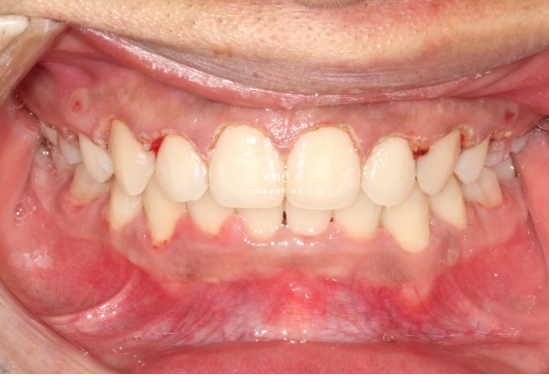

이제 전후 비교 보겠습니다.

중심선은 잘 맞으며 과개교합은 좋아졌습니다.

안모에서는 확실한 거미스마일 개선이 눈에 띕니다.

앞니가 상당히 뒤로 들어갔음에도 치료 전과 후 입매 변화가 크지는 않습니다.

인중 부위의 볼롬함 감소와 아랫입술의 후퇴 정도만 눈에 띕니다.

위 앞니 기준 뒤로 4-5mm 들어갔고 위로는 2-3mm 함입되었습니다.